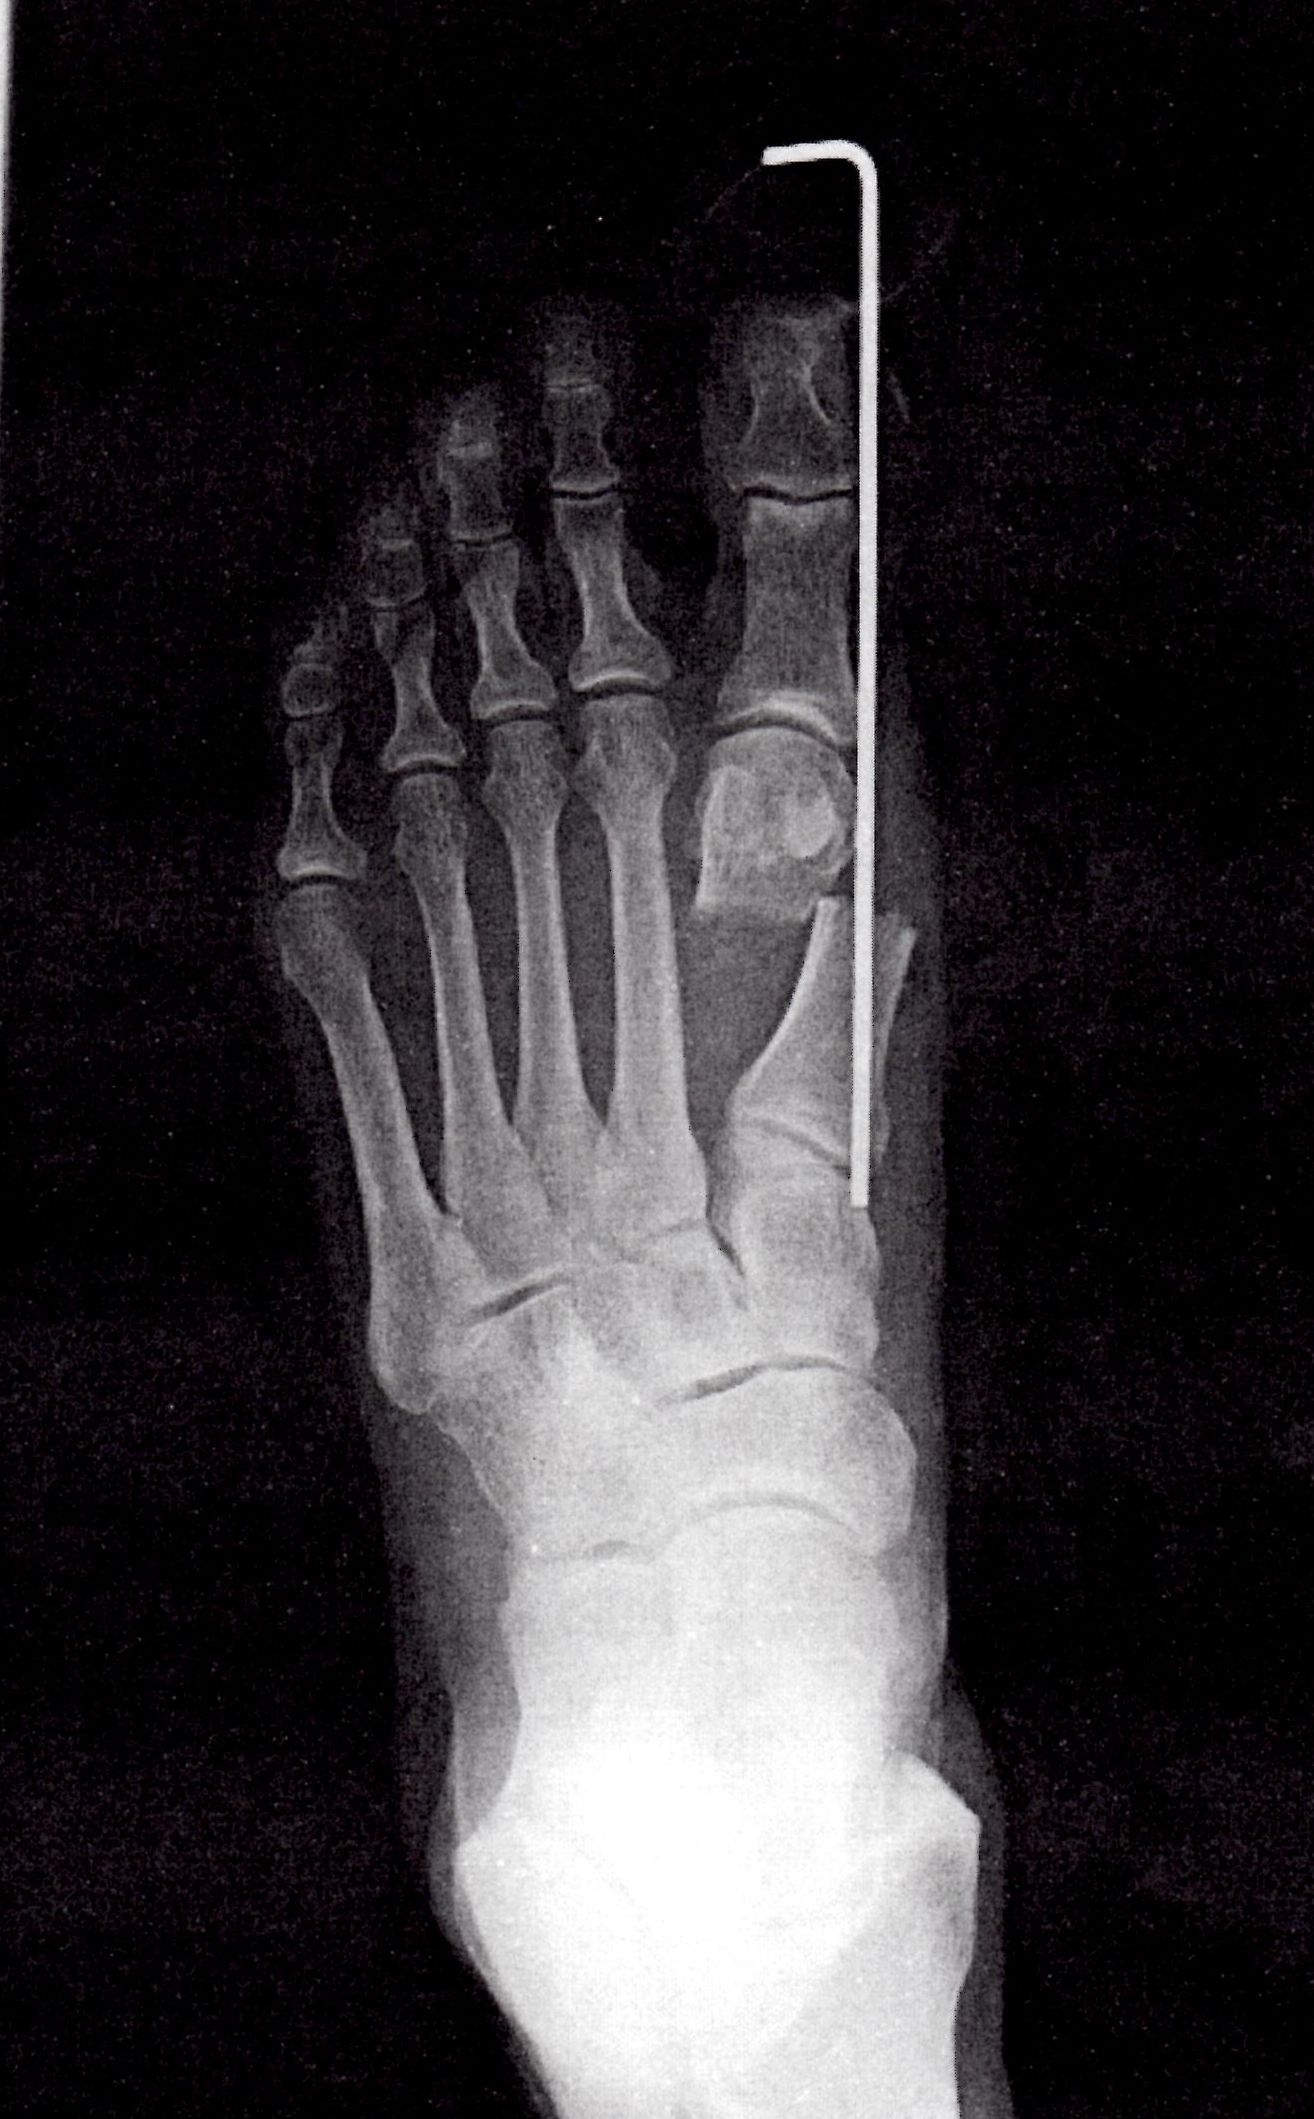

1月17日(金)左足の手術をしました。美しさとは程遠い写真ですすから小さくしました。慶応義塾大学病院でDLMO(デルモ)法で手術、日帰りです。右足は、5,6年前に手術し、左足は、保存療法で進行を食い止めようとしたのですが、徐々に進行してしまうので、日帰り手術ができる間にと思い、寒くて外に積極的にでたくない冬の時期を選びました。

私の場合は、既に右足を手術していますから、どうしても左右の足の形が違ってきていて、靴をオーダーすると左右のサイズが違ってしまいます。また、見てくれのこともあります。右足は綺麗ですが、左足がゆがんでしまいます。

現在、2週間経過、あと2週間で固定している金具を外せます。もう少しの辛抱です。